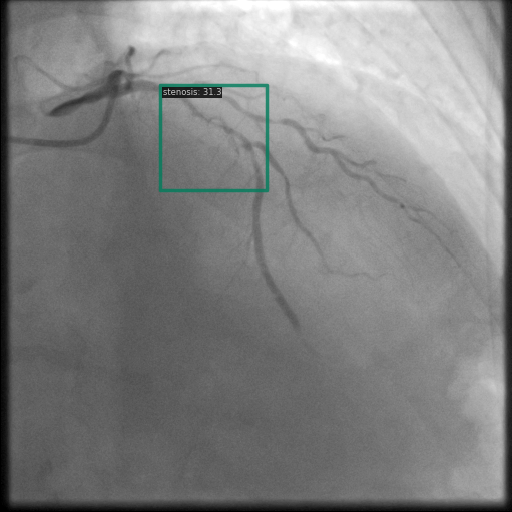

Figure 1 shows sample images from the ARCADE dataset with annotations for stenosis detection. The annotations highlight regions of arterial narrowing, providing ground truth data for training and evaluating object detection models.

To further assess the detection performance, qualitative results for three test images are presented in Figure 2. The first column shows the original images with ground truth annotations. The second, third, and fourth columns depict detections from DINO-DETR, Grounding DINO, and YOLO, respectively.

(a) Original (b) DINO-DETR (c) Grounding DINO (d) YOLO

The qualitative comparison in Figure 2 reinforces the trends observed in the quantitative evaluation. DINO-DETR produced fewer detections, occasionally missing relevant stenotic regions, consistent with its conservative detection strategy aimed at minimizing false positives [6]. Grounding DINO, although capable of identifying more regions, sometimes resulted in cluttered predictions due to over-detections [7]. YOLO provided a reasonable trade-off by effectively capturing anatomical structures while maintaining relatively high confidence scores and clear visualizations [5].